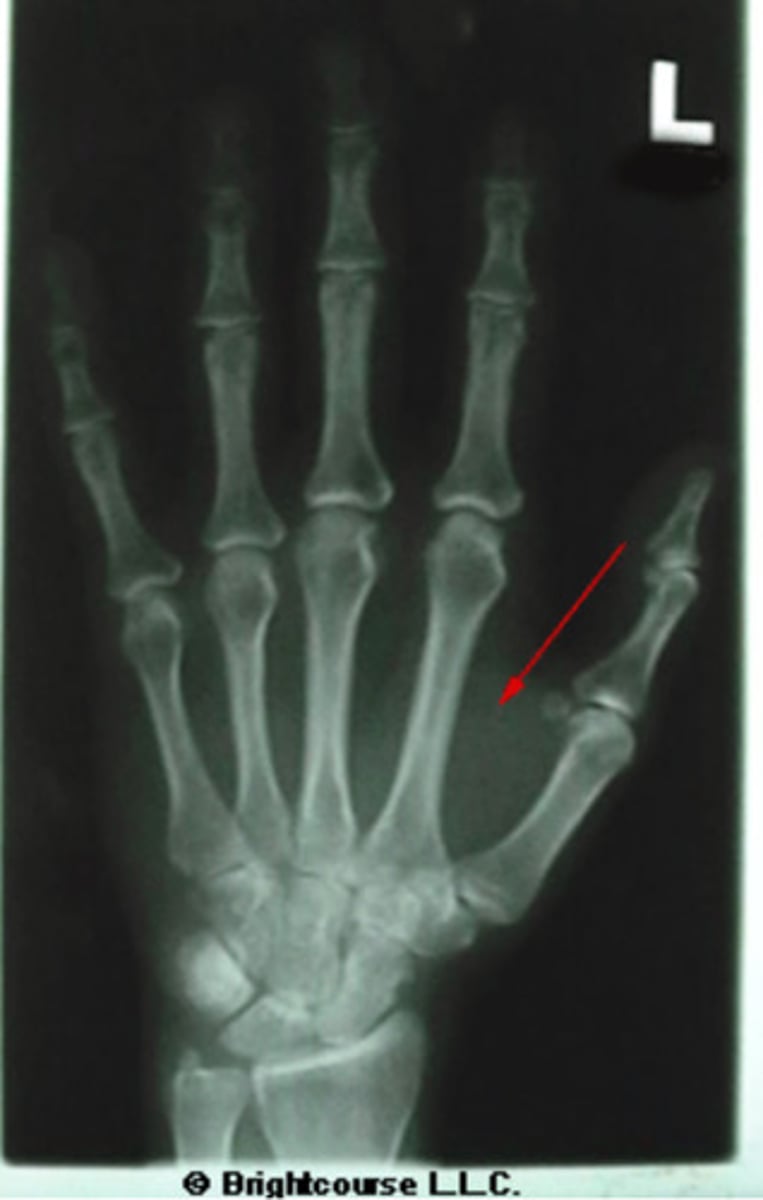

Soft tissue

What structure is being pointed out by the arrow?

Sesmoid bone